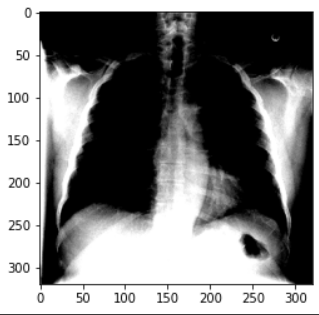

: 환자 32,717명의 108,948개 frontal-view X-ray 이미지가 포함된 ChestX-ray8 데이터셋을 사용

→데이터셋의 각 이미지에는 14개의 병리학적 상태를 식별하는 여러 텍스트 마이닝 레이블이 포함됨

*의사는 이 결과를 통해, 8가지 질병을 진단하는데 사용할 수 있음

→이 데이터에 기반하여 14개의 레이블이 지정된 병리 상태에 대한 분류 모델을 개발할 것

*각 병리에 대해 '양성' 또는 '음성'을 예측

2.2 Preparing Images

: 데이터셋 분할이 준비됐으므로, 이를 사용하도록 모델 설정을 진행할 수 있음

: 이를 위해, Keras의 ImageDataGenerator를 사용하여 데이터프레임에 지정된 이미지에 대한 'generator'를 빌드

: generator로 각 배치의 값을 변환하여 평균이 0, 표준 편차가 1이 되도록 표준화 함

: 또한, 단일채널 X-ray 이미지 (회색조)를 3채널 형식으로 변환

: 이미지 크기를 320x320 픽셀로 설정

Found 420 validated image filenames.: '__get_item __ (index)' 함수를 호출하여, generator가 모델에 제공하는 내용을 살펴봄

x, y = train_generator.__getitem__(0)

plt.imshow(x[0]);

# Expected output

Clipping input data to the valid range for imshow with RGB data ([0..1] for floats or [0..255] for integers).